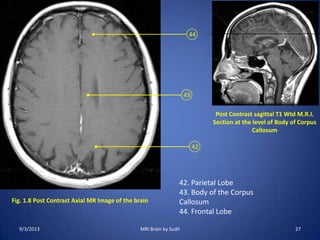

Fig. 1.8 Post Contrast Axial MR Image of the brain

Post Contrast sagittal T1 Wtd M.R.I.

Section at the level of Body of Corpus

Callosum

42. Parietal Lobe

43. Body of the Corpus

44. Frontal Lobe